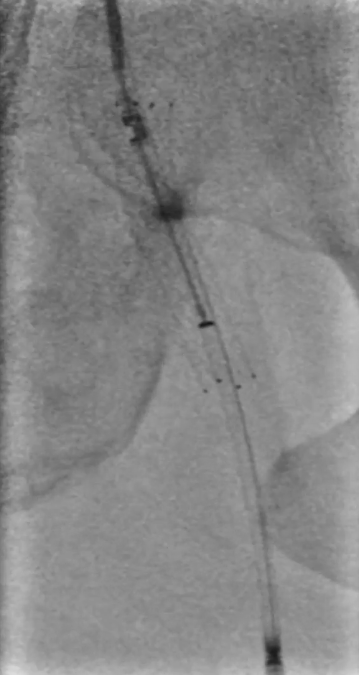

穿刺与造影定位

穿刺右侧股总动脉,置入8F翻山鞘,行左下肢动脉造影,可见左股浅动脉长段闭塞,远端流出道尚通畅。

既往支架已遮盖股浅动脉起始段